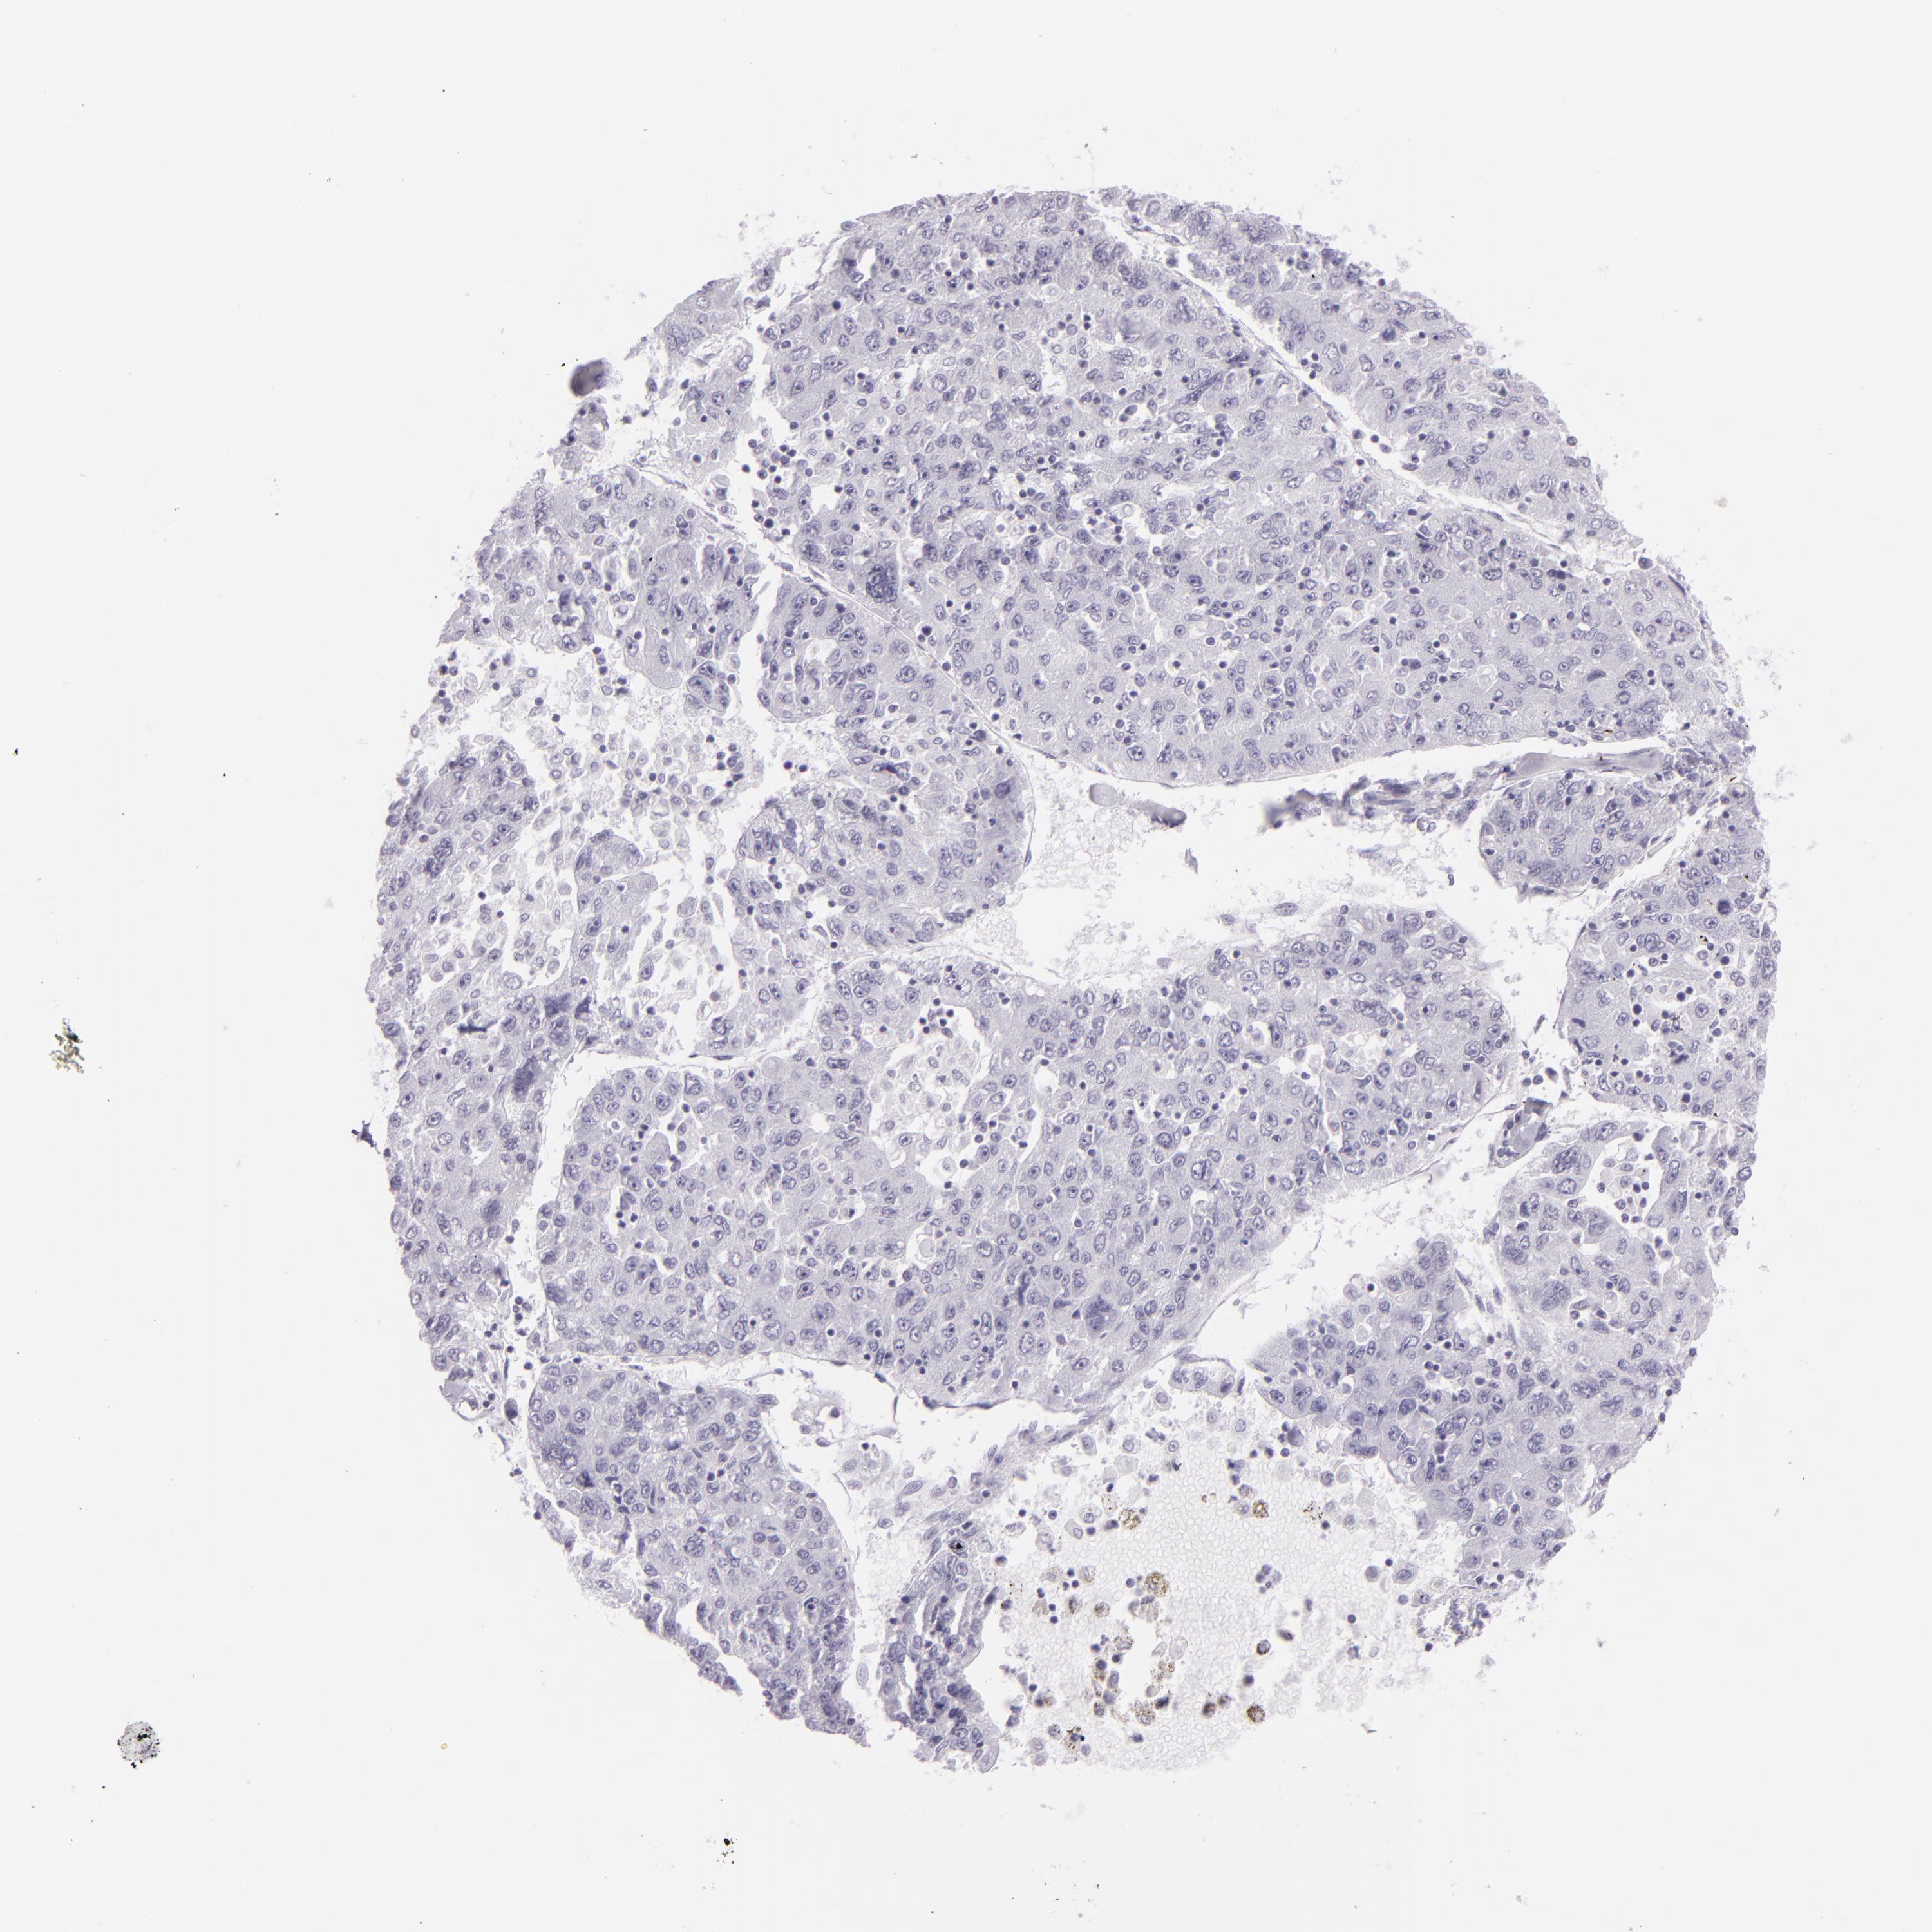

LIVER CANCER - Protein expressioni

A mouse-over function shows sample information and annotation data. Click on an image to view it in a full screen mode. Samples can be filtered based on level of antibody staining by selecting one or several of the following categories: high, medium, low and not detected. The assay and annotation is described here.

Note that samples used for immunohistochemistry by the Human Protein Atlas do not correspond to samples in the TCGA dataset.

Antibody stainingi

Antibody staining in the annotated cell types in the current human tissue is reported as not detected, low, medium, or high, based on conventional immunohistochemistry profiling in selected tissues. This score is based on the combination of the staining intensity and fraction of stained cells.

Each image is clickable and will lead to virtual microscopy that enables deeper exploration of all samples and also displays staining intensity scores, fraction scores and subcellular localization as well as patient and tissue information for each sample.

Antibody CAB002165

Staining

High

Medium

Low

Not detected

Intensity

Strong

Moderate

Weak

Negative

Quantity

>75%

75%-25%

<25%

None

Location

Nuclear

Cytoplasmic/membranous

Cytoplasmic/membranous,nuclear

Carcinoma, Hepatocellular, NOS

Cholangiocarcinoma